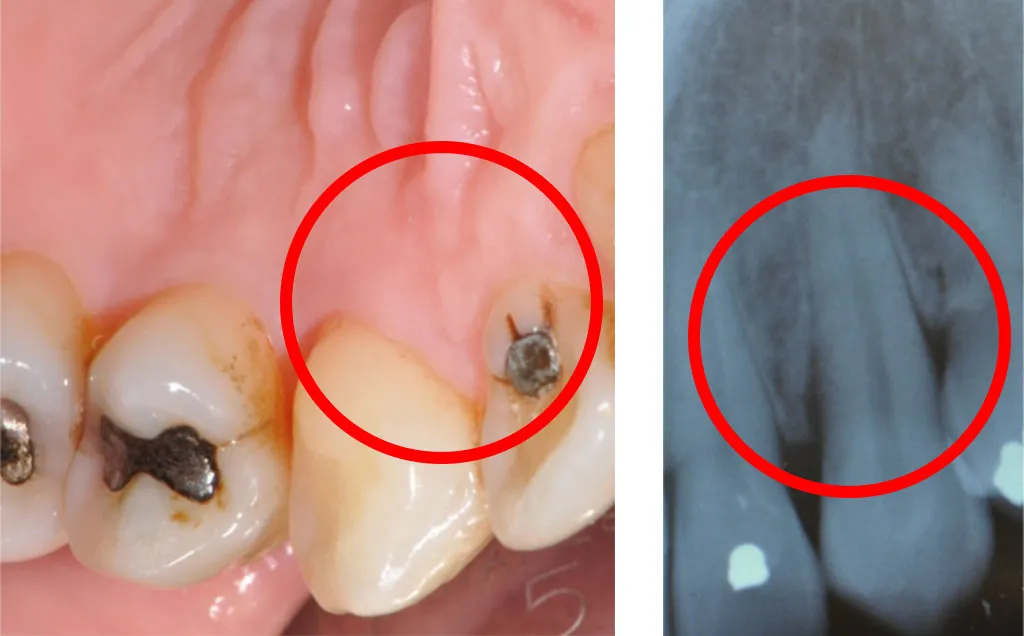

Il primo segno di malattia parodontale invece è la tasca parodontale (Fig. 3). L'infezione microbica dovuta all'accumulo di placca e tartaro nel solco gengivale ha causato una risposta infiammatoria tale da distruggere l'attacco epiteliale prima e quello connettivale poi consentendo ai batteri di migrare in profondità. La tasca si rileva tramite il sondaggio che evidenzierà profondità maggiori di 3mm e spesso sanguinamento. Maggiore sarà la profondità di sondaggio più grave sarà la malattia e anche l'osso alveolare potrà essere compromesso dal riassorbimento. Questo causerà mobilità più o meno grave del dente e a volte formazione di ascessi parodontali. Il margine gengivale potrebbe essere mantenuto nella sua posizione normale (Fig.3) se l'osso al di sotto non è troppo riassorbito, mentre sarà visibile una recessione (retrazione) della gengiva se l'osso sottostante è gravemente compromesso (Fig.4).